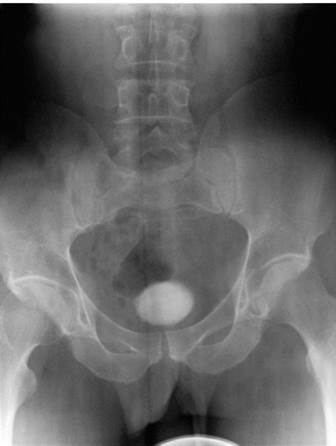

С помощью обзорной рентгенографии таза можно увидеть тень конкремента в проекции мочевого пузыря, оценить его размеры, получить представление о плотности его структуры, что важно для определения способа камнедробления (рис. 10.9).

Рис. 10.9. Обзорный снимок мочевой системы. Камень мочевого пузыря

Несмотря на важность информации, получаемой при выполнении обзорной рентгенографии, следует помнить, что камни мочевого пузыря, содержащие соли мочевой кислоты (ураты), не задерживают рентгеновские лучи и не выявляются при этом исследовании. Обзорный снимок позволяет определить количество камней и их размеры.